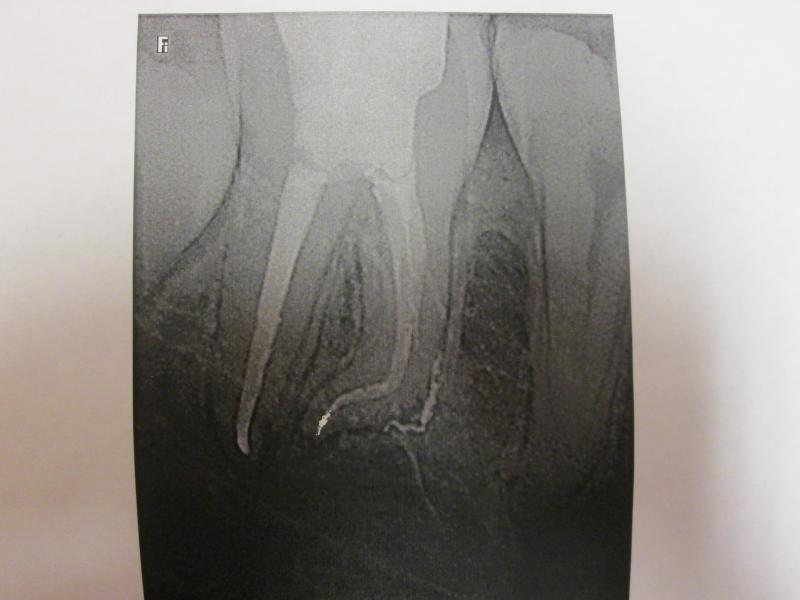

**PLEASE BE AWARE THAT  A ROOT CANAL IS AN ATTEMPT TO SAVE YOUR ALREADY DAMAGED TOOTH.  THERE IS NO GUARANTEE THAT ANY TOOTH CAN BE SAVED BUT DR JET WILL DO HIS BEST TO HELP YOU. THE OTHER OPTION IS TO EXTRACT YOUR TOOTH